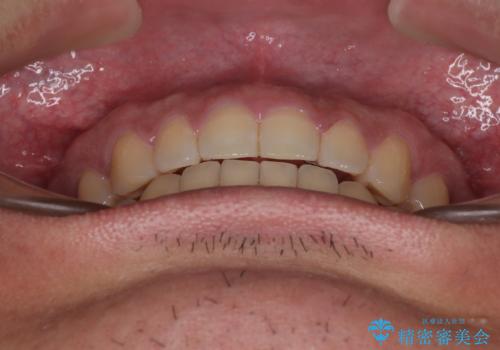

舌のトレーニングをしっかりと行ってくださったおかげで、順調に治療を終えることができました。

舌の突出癖が速やかに改善され、後戻りによるスペースは今のところ認められておりません。